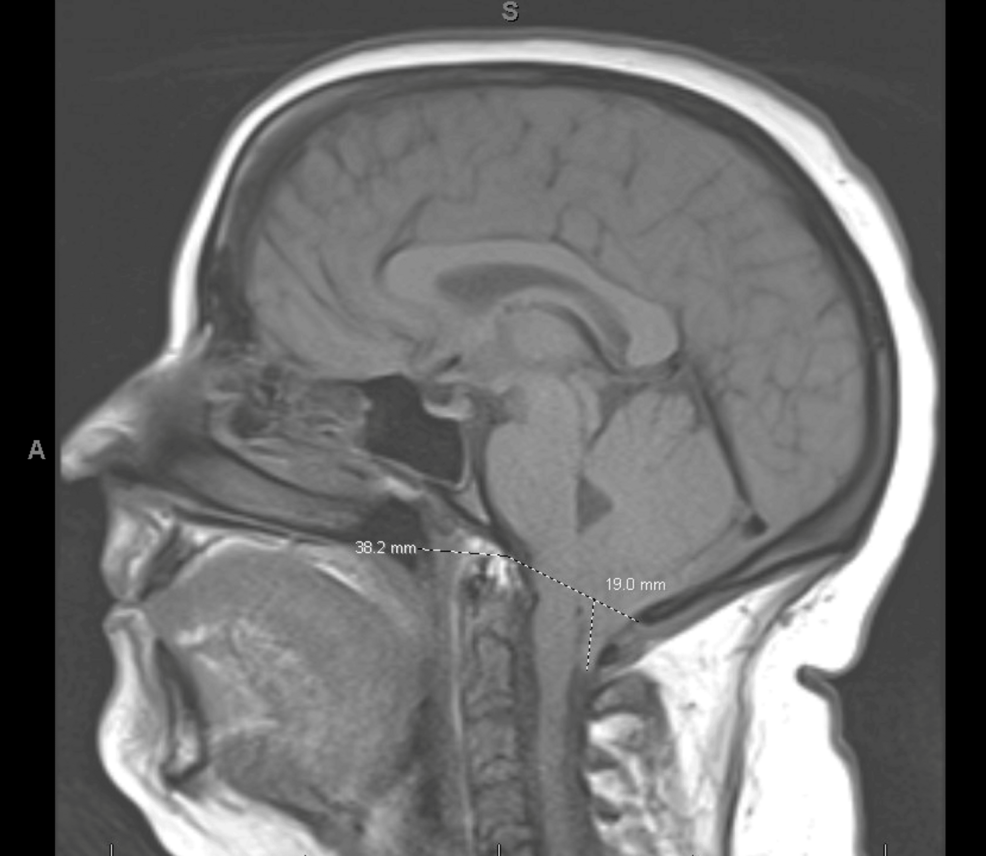

Initial assessments focused on potential causes directly related to the leukemia or its treatment. Though, comprehensive neurological evaluations, including magnetic resonance imaging (mri), revealed the confluence of multiple factors. The Chiari malformation,previously known,appeared to be contributing to the headache burden,while the migraines added another layer of complexity. Distinguishing between these sources of pain, and determining whether the leukemia itself was exacerbating the symptoms, proved to be a significant hurdle.

* Diagnostic Considerations: Headaches associated with Chiari malformation are frequently enough occipital (back of the head) and worsened by coughing, straining, or bending over. MRI of the brain and spine is crucial for diagnosis.